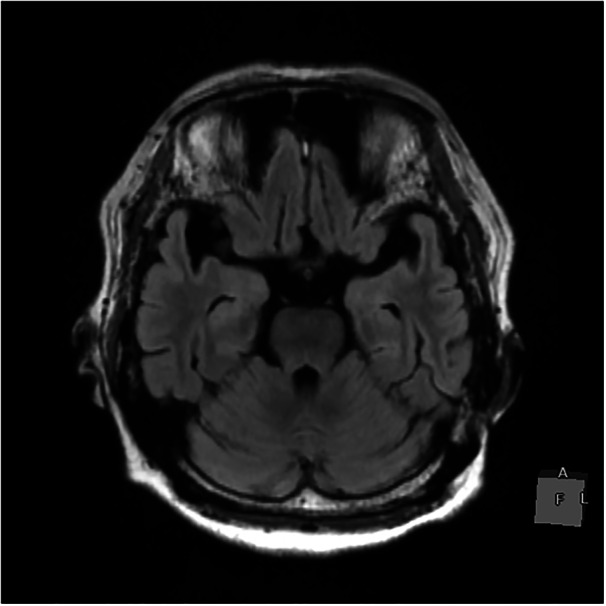

Case presentation: We present a case of catatonia associated with schizophrenia complicated by NCSE. A 77-year-old woman with a 30-year history of well-controlled schizophrenia developed stupor and was admitted to our hospital. EEG revealed evolving spike-and-wave complexes, leading to a diagnosis of NCSE. Administration of levetiracetam improved the EEG findings, and subsequent monitoring confirmed resolution of epileptiform activity. However, the patient's stuporous state persisted despite the normalized EEG. Extensive workup showed no evidence of encephalitis or other neurological pathology. We diagnosed her with NCSE and catatonia associated with schizophrenia. Electroconvulsive therapy (ECT) was administered, resulting in complete resolution of the catatonic symptoms.